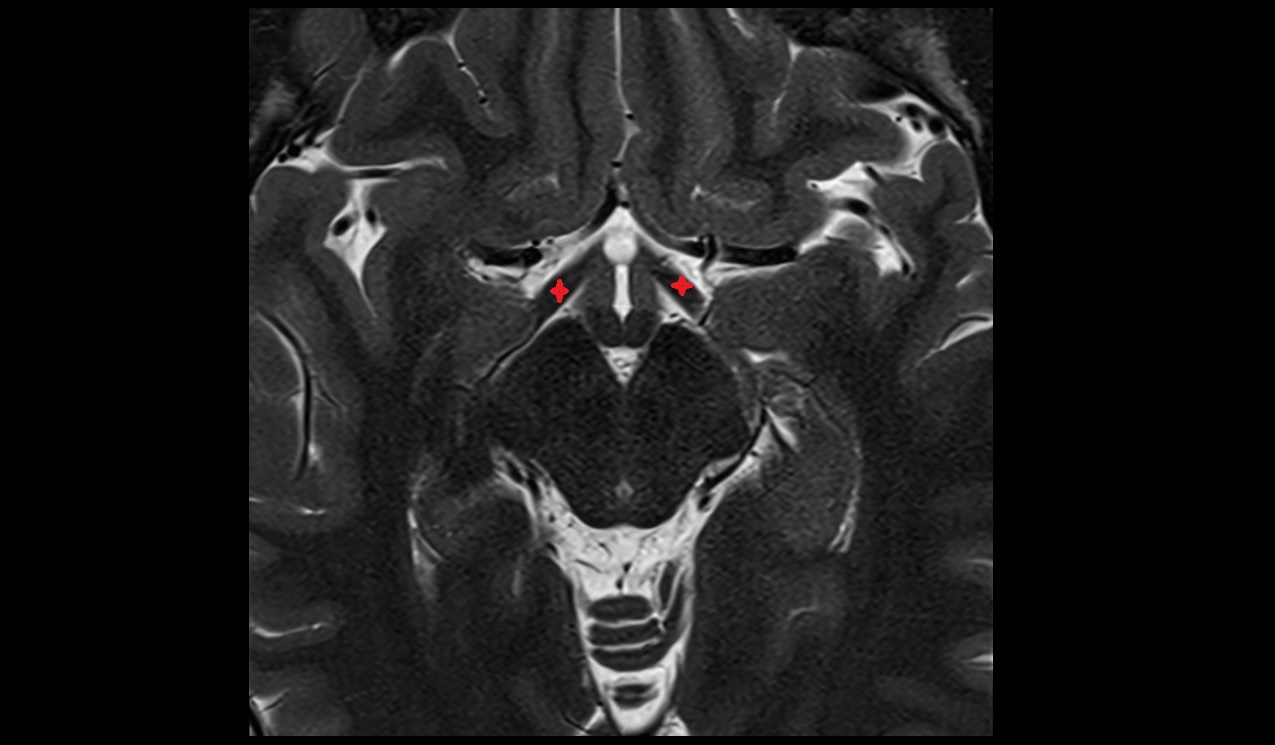

- Middle cerebral artery horizontal segment (M1)

- Middle cerebral artery insular segment (M2)